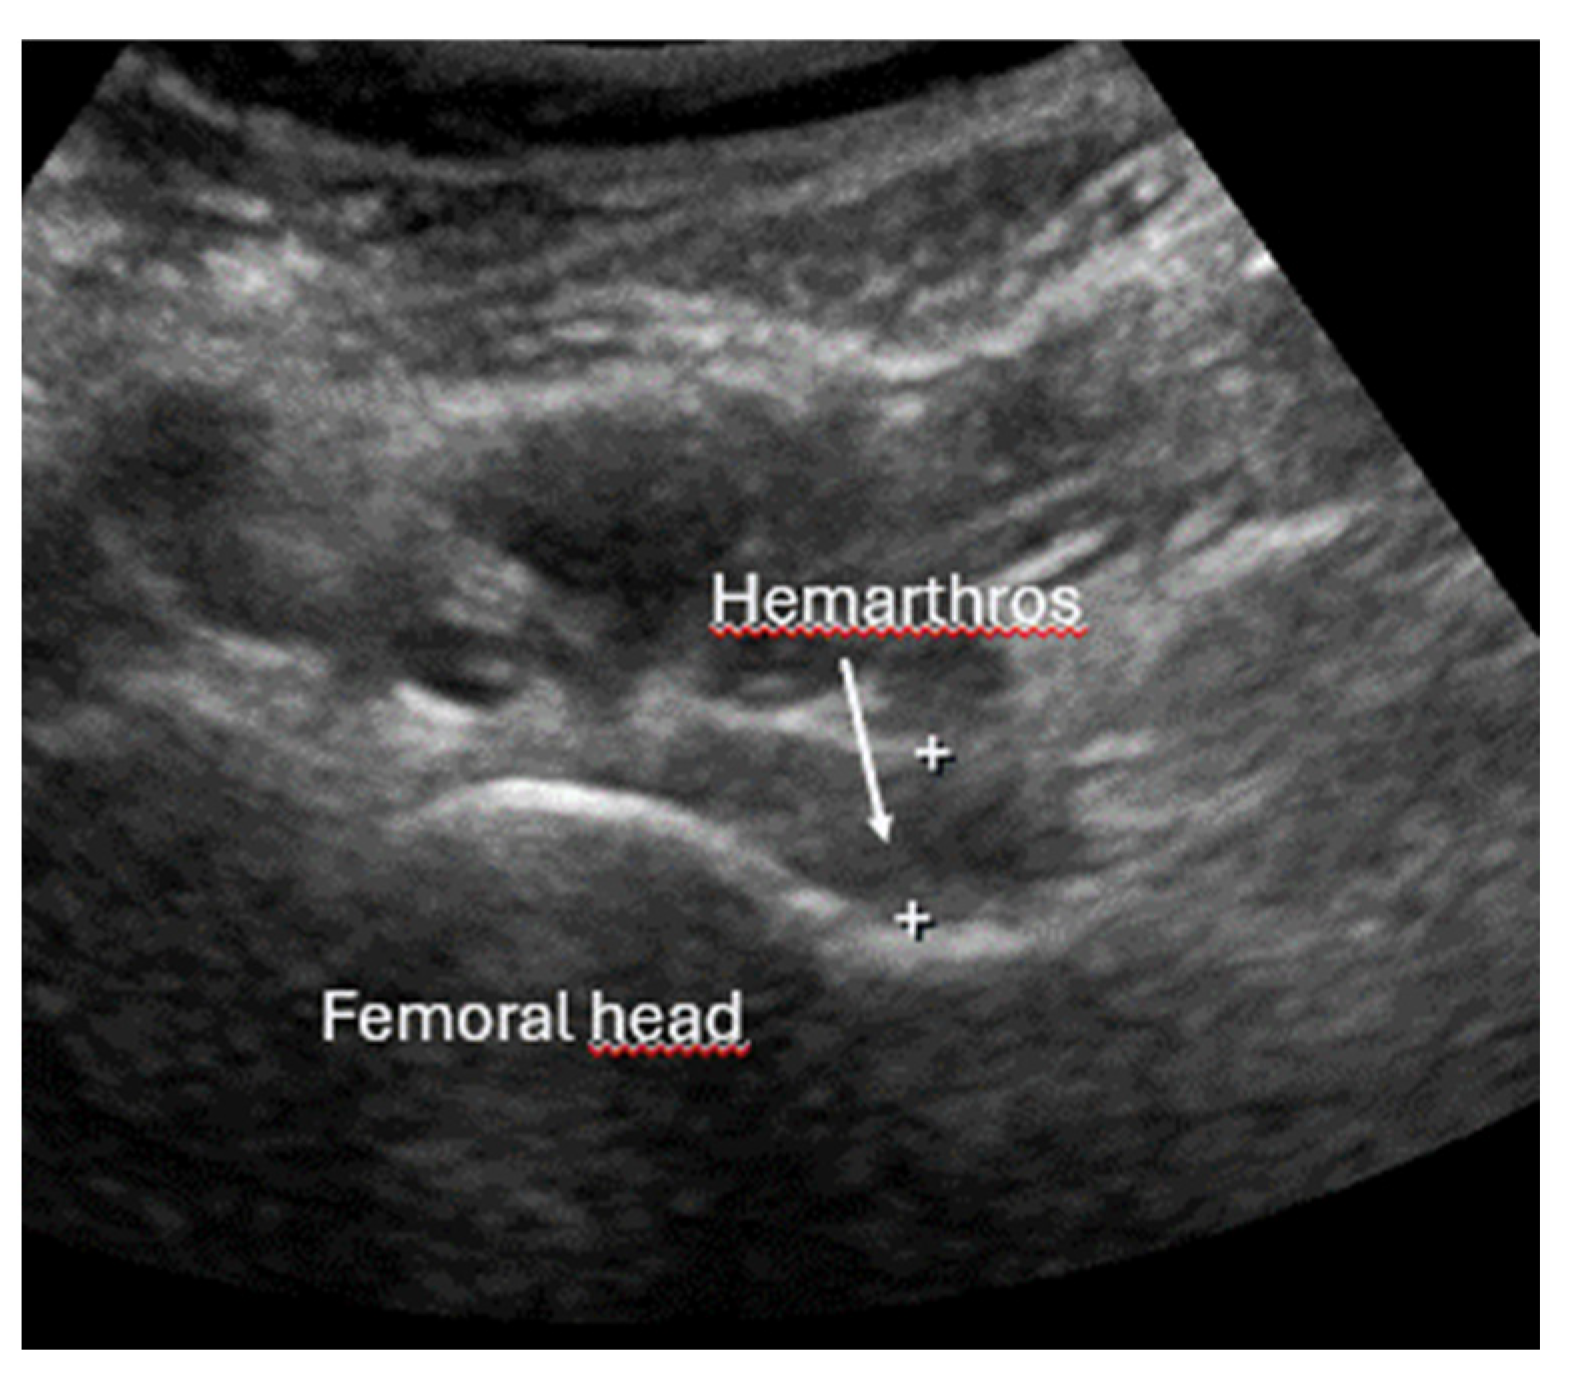

- Joint effusion and liphemarthrosis: fluid accumulation within a joint, sometimes containing fat droplets, which often indicates an intra-articular fracture.

- Safran, O.; Goldman, V.; Applbaum, Y.; Milgrom, C. Posttraumatic painful hip: Sonography as a screening test for occult hip fractures. J. Ultrasound Med. 2009, 28, 1447–1452. [Google Scholar] [CrossRef]